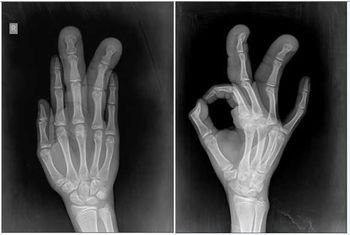

MacrodactylyByPratiksha Yadav, MDNovember 15th 2013Case History: A 12-year-old girl presented with history of enlargement of middle and ring fingers of right hand since birth.